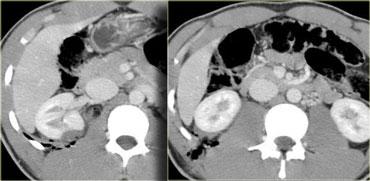

Trước tiên hãy quan sát các hình ảnh bên trái của bệnh nhân bị chấn thương thận sau chấn thương kín.

Phân độ chấn thương CT là bao nhiêu?

Câu trả lời là, giống như tất cả các hệ thống phân độ, hệ thống này cũng có những hạn chế.

Những gì chúng ta thấy bên trái không phải là vết rách, vì nó không có dạng tuyến tính.

Đây cũng không phải là đụng dập, vì ranh giới rõ nét.

Đây là nhồi máu phân thùy thận sau chấn thương.

Bên trái là hình ảnh điển hình của khối máu tụ dưới bao thận, cũng là chấn thương thận độ I.